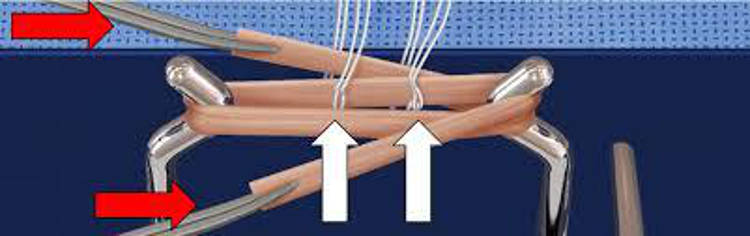

και η τοποθέτηση αυτού γίνεται μέσα από την άρθρωση του γόνατος όπου με ειδικά εργαλεία δημιουργούνται τούνελ στο μηρό και στη κνήμη από μέσα από την άρθρωση προς τα έξω.

Άρα τα τούνελ είναι πλέον μικρότερα σε μήκος από τις σύνηθες τεχνικές με αποτέλεσμα να μην πειράζουμε το έξω τμήμα του οστού (corticalis), η απώλεια οστού είναι αρκετά λιγότερη και τα μαλακά μόρια προφυλάσσονται στο μέγιστο.

Η καθήλωση του τένοντα γίνεται και στο μηρό και στη κνήμη με μκρά φύλλα τιτανίου μήκους ενός εκατοστού και πάχους ελαχίστων χιλιοστών που βρίσκονται εκτός οστού. Έτσι μέσα στο οστό δεν υπάρχει ξένο σώμα εκτός από τα ράμματα.

Μας δίνεται η δυνατότητα κατά τη διάρκεια του χειρουργείου να ελέγξουμε τη τάση του μοσχεύματος και να τη ρυθμίσουμε έτσι ώστε να κερδίσουμε τη βέλτιστη τάση για να αποκτήσει το γόνατο άριστη σταθερότητα.